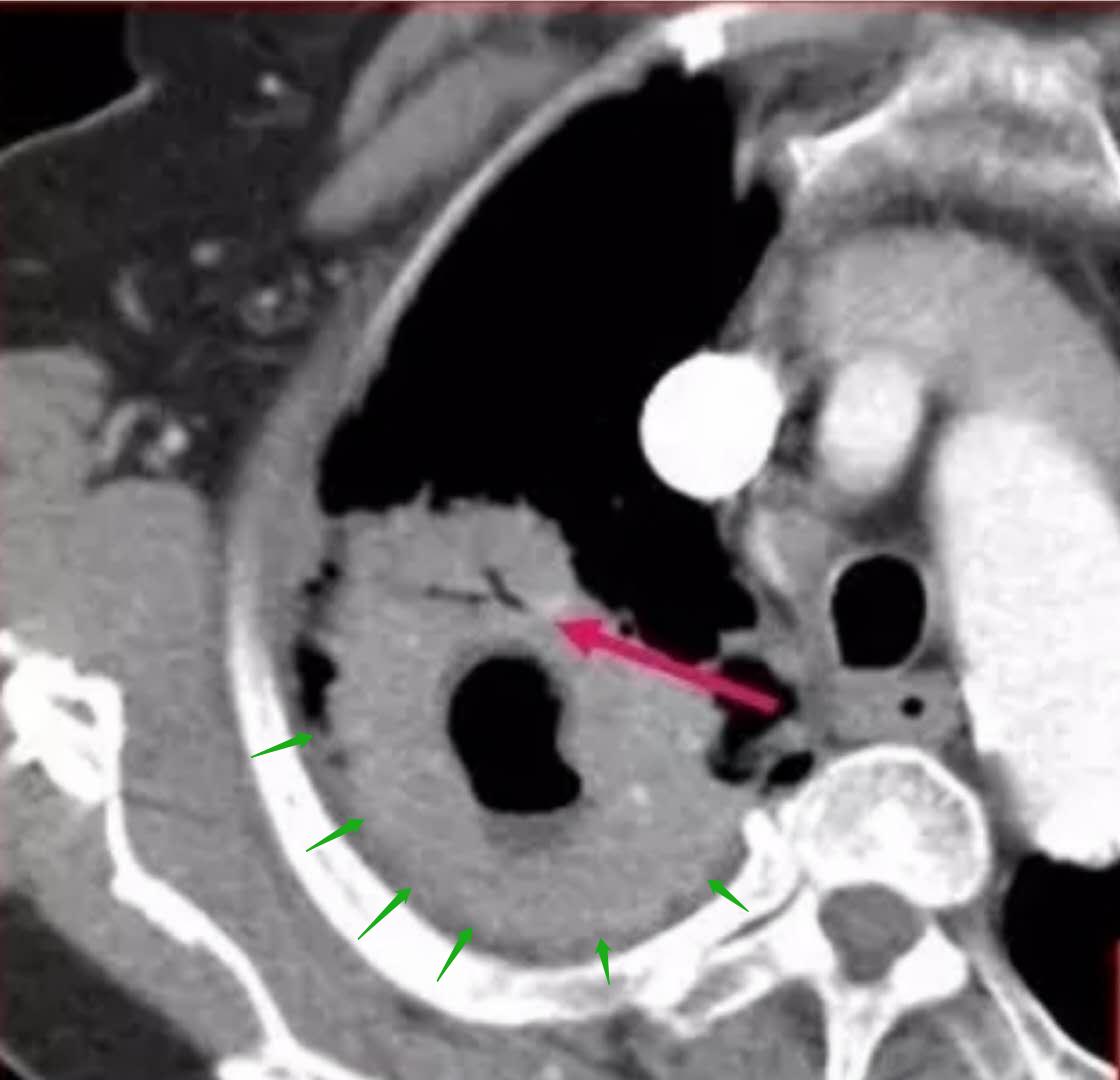

像上图这位老人,76岁,咳嗽、呼吸急促一个月,CT发现右肺巨大肿块,可见平行的支气管,增强扫描强化均匀,但经支气管镜证实,这是肺鳞癌合并了感染。

所以,发现此类病例,如果抗生素治疗后病灶基本吸收了,就没事了;如果病程反复迁延,时好时坏,进一步检查也是有必要的,比如支气管镜或者经皮肺穿刺等手段。